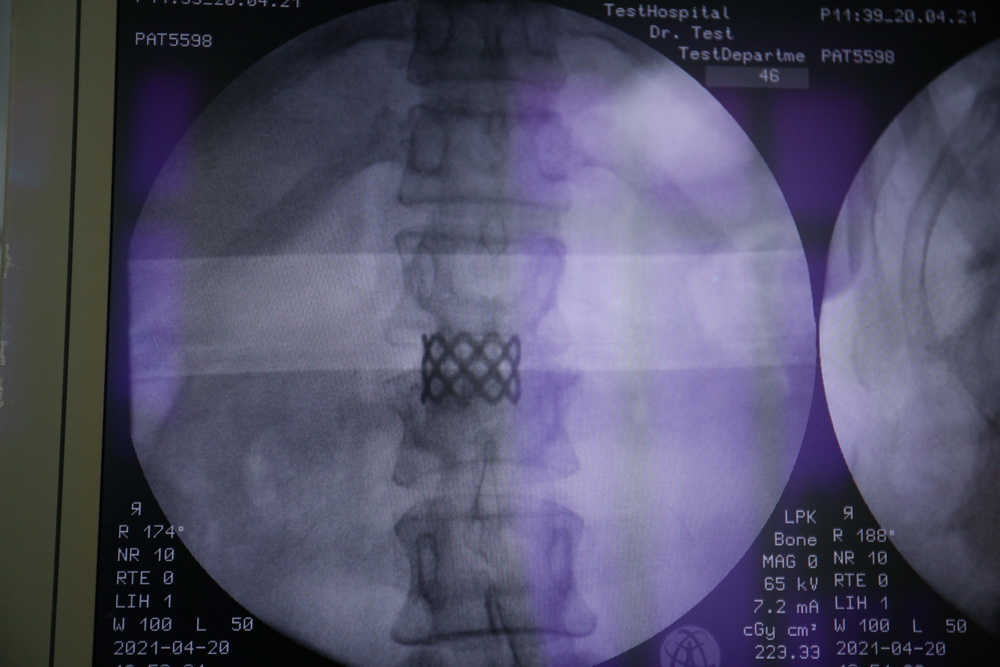

Хирургия позвоночника ― одно из главных направлений Новосибирского научно-исследовательского института травматологии и ортопедии. Основатель новосибирской школы вертебрологии — профессор Яков Лейбович Цивьян. Травма позвоночника ― одно из ключевых и социально значимых направлений. Для успешного лечения пациентов с такими травмами в НИИТО применяют весь арсенал современных хирургических технологий.

Для начала пациента осматривает бригада специалистов, далее по показаниям проводят дополнительную лучевую диагностику: рентгенографию, МРТ, МСКТ. По снимкам врачи уточняют диагноз и определяют тактику лечения. Не при всех травмах требуется оперативное лечение, только при самых тяжёлых.

Если пациент стабилен и его жизни ничего не угрожает, приступают к операции на позвоночнике. Самое главное ― как можно скорее устранить компрессию спинного мозга или его корешков, а также убрать все виды смещения. От скорости и правильности этого этапа помощи зависит всё дальнейшее выздоровление пациента.#SHOWMORE__406663#

Перед операцией делают рентген и МРТ позвоночника. После этого врачи определяют тактику процедуры. Во время операции ставят металлическую конструкцию. Её вставляют в позвоночник, а в шурупы вкладывают стержни. Сначала стержни повторяют деформацию, но их разворачивают, и конструкция встаёт по естественным изгибам тела. Потом позвоночник между отдельными шурупами стягивают или растягивают, чтобы он встал ровно.